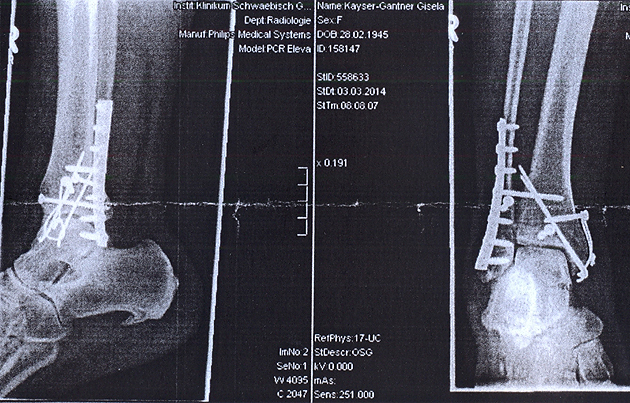

Mit schnellem Schritt durchquerte ich mein Wohnzimmer, um sie daran zu hindern, ihre feste Hinterlassenschaft auf die Terrasse zu setzen. Hat funktioniert - aber mein Ausfallschritt nach vorn riß mich zu Boden und zerlegte mein Sprunggelenk in zwei Teile. Das sieht aber nicht richtig aus, fuhr mir durch den Kopf, und ich schob beide Stücke wieder aufeinander.

Ende der Geschichte: Zweieinhalb Stunden Notoperation, eine Woche schmerzhaftes Krankenhaus, neun Wochen keine Belastung des rechten Beines und ... und ...